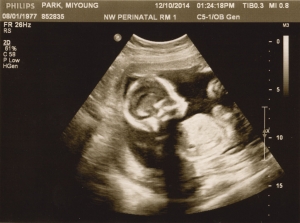

Last Ultrasound